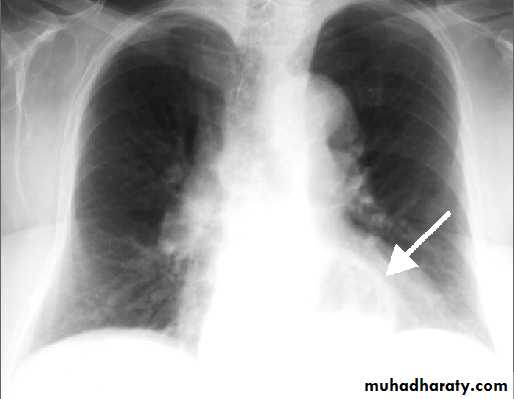

Lingular consolidation-PA. Patchy effacement of the left heart border.

chest practice

Left upper lobe consolidation-Lat.

The opacification is sited anterior to the obliq- fissure-the position of the upper lobe.